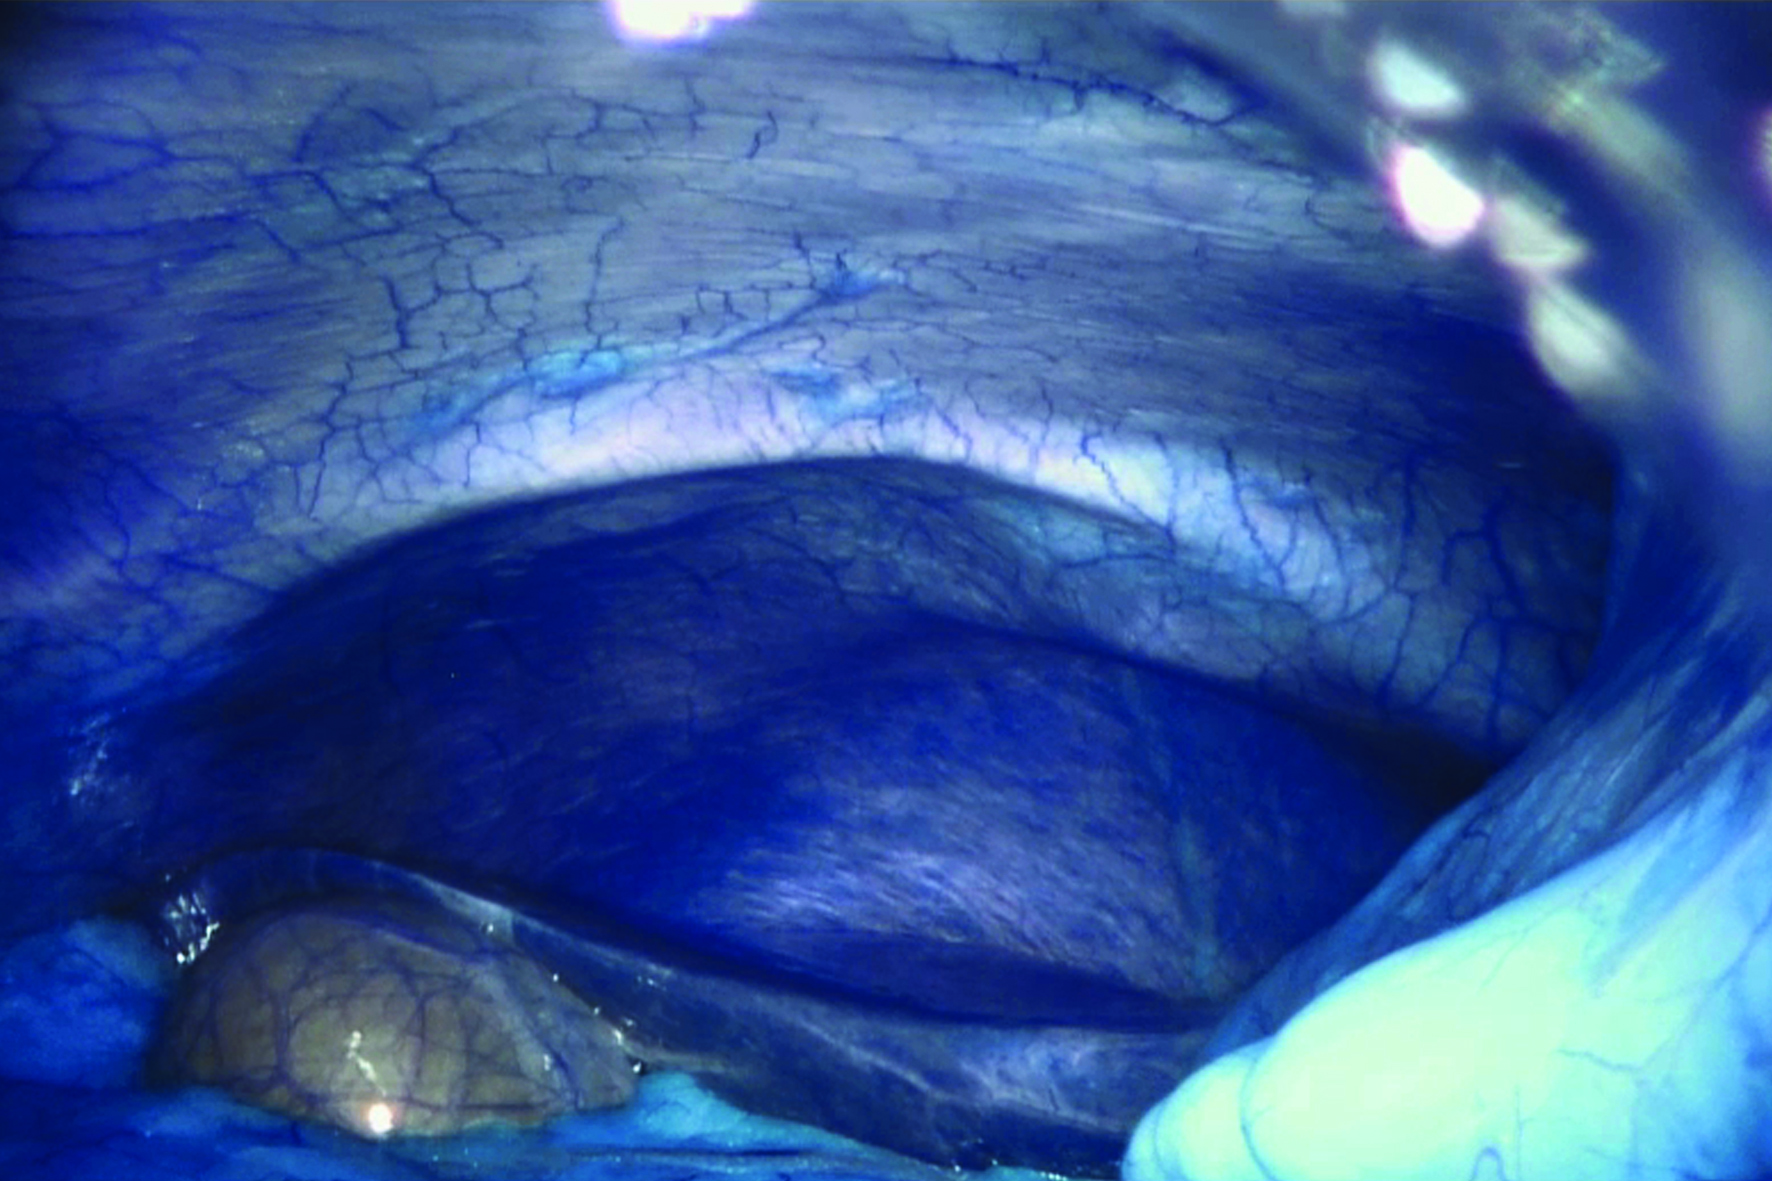

Dit laatste deel van Ancarani’s trilogie speelt zich af in een operatiekamer, waar een wonderlijke reis door het lichaam wordt gemaakt, uitgevoerd door robotarmen met de chirurg achter een soort joystick. Het geheel roept sciencefictionachtige associaties op met Fantastic Voyage (1966). Ancarani brengt de hele operatie, wonderschoon uitgelicht (zonder bloederige effecten), als een duizelingwekkende choreografie met minuscule precisie in beeld, met bijzonder spannende soundtrack.